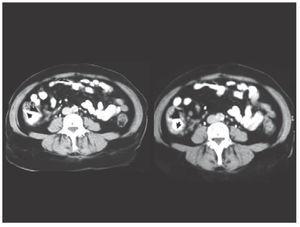

The patient was treated with oral metronidazole for 14 days, showing good clinical recovery and was discharged after two weeks due to persistent abdominal pain within the first week after starting anti-parasitic drugs and completing the diagnostic approach. During follow-up a colonoscopy was performed showing a normal cecum mucosa except for some areas of focal hyperaemia (Figure 3). The control CT scan four weeks after treatment was completely normal.

¿ Figure 3. Follow-up colonoscopy showing normal mocosa and some foci of hyperaemia (arrows) in the cecum wall.